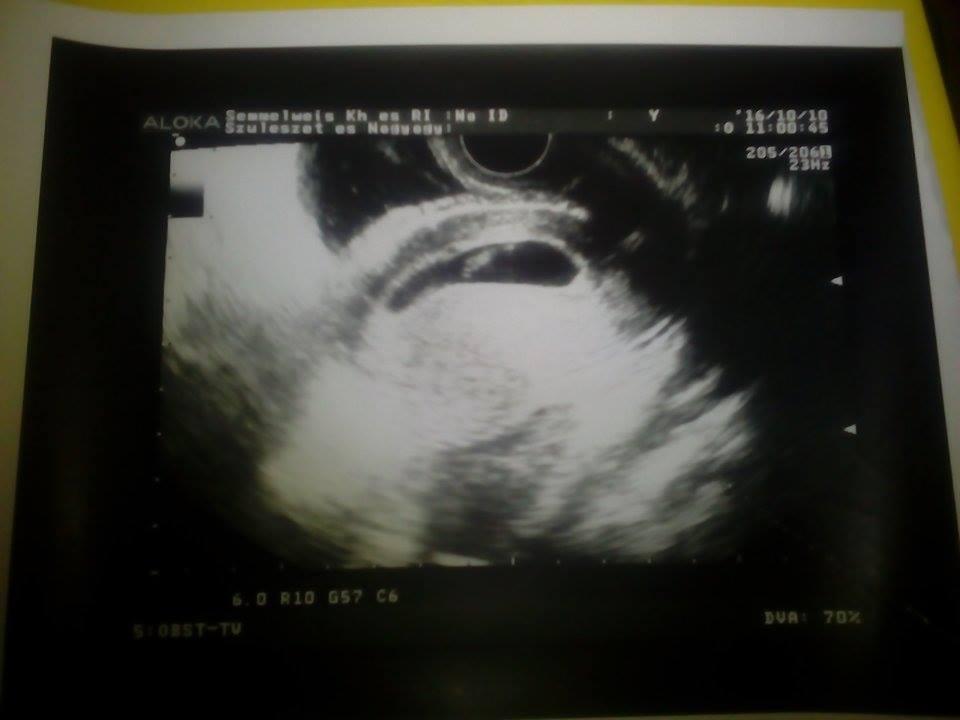

Megjártam ma a dokit. Kicsit fura volt, megvizsgált, majd elküldött uh-ra és azt mondta, hogy ha az uh-n minden oké nem kell hozzá vissza mennem. De ez nem az a doki volt akihez én járok, mert ebben az időben ő nem tudot fogadni, de amint tudok elmegyek hozzá is.

A mi csodababánk jelenleg 7 hetes és 9 mm. Nagyon boldogok vagyunk. ![]()

Nagyon cuki a fotó. Olyan kis almamag még. Jó egészséget. Szép várandóságot Neked. Mikorra vagy kiírva?